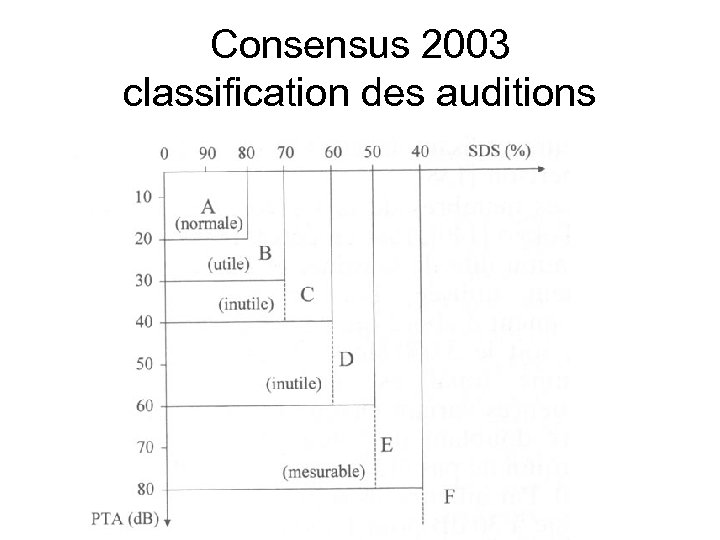

Consensus 2003 classification des auditions

Consensus 2003 classification des auditions